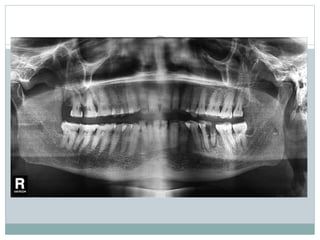

Various portals of entry of bacteria into pulp